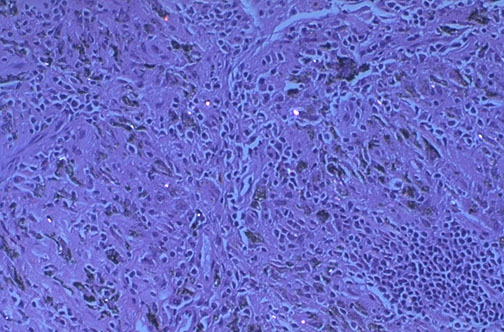

Small amounts of inhaled dusts may contain silica, which is transferred to hilar lymph nodes, along with carbon pigment, to produce this pattern of "silicoanthracosis" a common but clinically insignificant finding.